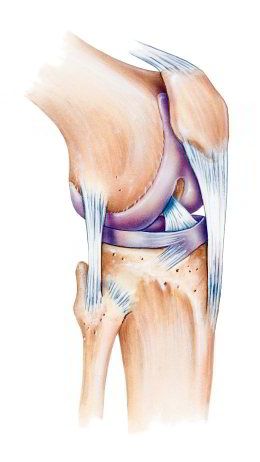

Kniescheibe mit Bändern,

Schema Seitenansicht Kniescheibe mit Bändern, Schema Seitenansicht [2] und von vorn [3]

-- die Kniescheibe ist eine etwas dreieckige Scheibe mit Wölbung zum Schutz des Knies

-- die Kniescheibe wird von Sehnen oben und unten gehalten, oben am Oberschenkelmuskel angesetzt, unten am Schienbein angesetzt

-- dank der Kniescheibe und den Sehnen kann man das Bein in leichter Weise strecken

-- die Rückseite der Kniescheibe hat eine Knorpelschicht für das Gleiten beim Beugen und Strecken des Beines

-- im Alter bildet sich die Knorpelschicht zurück, so beginnt oft eine Kniearthrose

-- Schäden an der Kniescheibe können sein: Fehlbildung, Bruch, Entzündung [web01]

-- die Kniescheibe bewegt sich in einer Art Rinne (Trochlea) des Oberschenkelknochens [web04,web05].